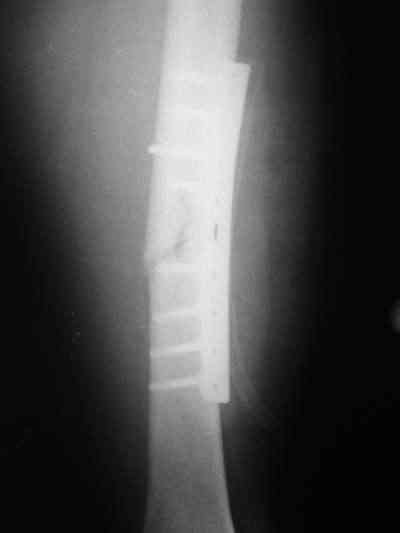

Около 10 дней назад выполнил остеосинтез бедренной кости LC-DCP и DHS по поводу фрагментарного оскольчатого перелома в средней трети и чрезвертельного перелома.

Снимки в приложении.

В приложении и имеющийся в наличии брейс. Приношу извинения за низкое качество снимков.

Качество снимков приемлемое. С нагрузкой категорически не надо спешить - только при уверенных рентгенологических признаках сращения на обоих уровнях в данном случае. Т.е. не только на диафизе, но и в вертельной области. При безупречном синтезе DHS ранняя нагрузка в этой зоне была бы безопасна, все определялось бы сращением диафиза. А поскольку винт в DHS сделали ну о-очень короткий, то ойкнуть не успеете, как

Глубокоуважаемый Никита!На бедре стоило бы обязательно провести межфрагментарный стягивающий винт и предварительно надо бы слегка изогнуть пластину,ну и может быть трансплантат по внутренней поверхности.А параллельно большому винту DHS провести спонгиозный винт для ротационной стабильности.Так,что с нагрузкой не нада тараписся!

Уважаемый Никита, очень меня расстроило не качество снимков, а сам остеосинтез. Вертельный перелом, пожалуй, еще срастется. А диафиз может преподнести ожидаемое, предуготованное осложнение: несращение и перелом импланта, даже если это суперфмрменная пластина.:(